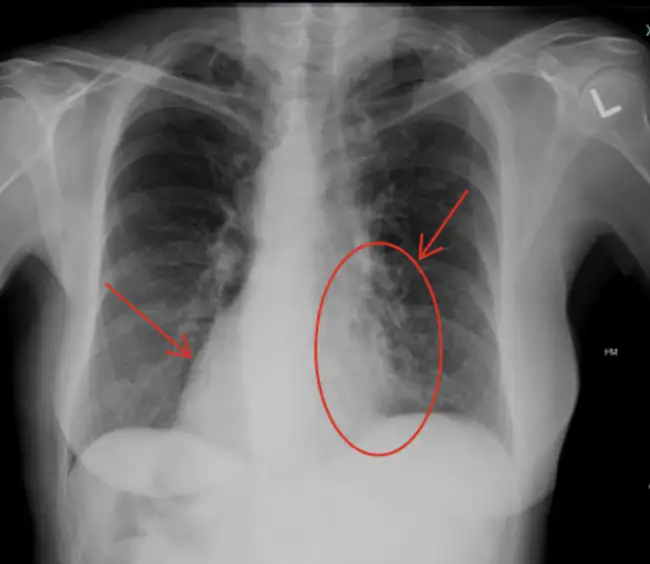

X-ray findings include prominent circular markings on the left lung base which are consistent with bronchiectasis. A closer look at the x-ray reveals that the heart is seen on the right side of the thoracic space, suggesting situs inversus. Situs inversus refers to the mirror-image arrangement of thoracic and abdominal organs and has no serious adverse health consequences by itself. However, in the context of chronic bronchiectasis and sinusitis, it is strongly suggestive of Kartagener syndrome. Kartagener syndrome is a subgroup of Primary Ciliary Dyskinesia (PCD) with a prevalence of approximately 1 in 20,000 to 40,000 individuals. Patients often present with recurrent respiratory infections, chronic sinusitis, and chronic and productive cough, while male patients may have a history of infertility due to immotile sperm.

- X-ray imaging often shows bilateral, lower-lobe–predominant bronchiectasis and associated findings include situs inversus.